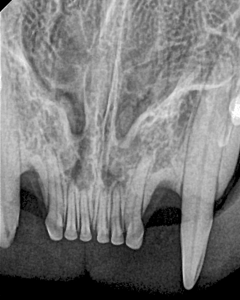

Canine Full Mouth Radiograph Example